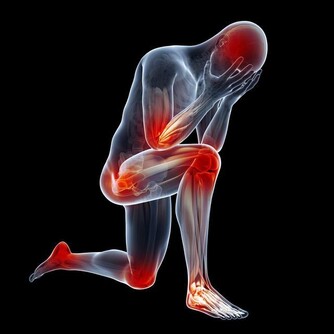

3. 你有壓力——可能是抑鬱症

我們的身體是一台不可思議的儀器,總能創造奇蹟,但它也會出問題。比如,當我們長期處於壓力狀態時,會陷入戰鬥模式,並且會分泌大量腎上腺素(幫我們避免危險)以及大劑量的皮質醇,這種激素能幫助我們恢復能量儲備並儲存脂肪,於是你會變胖。